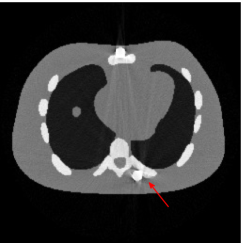

Figure 7(a) shows that the reconstructed NCAT phantom from FBP has severe metal artifacts and is noisy. The reconstructed image from the unweighted JSR model (3.2) shown in Figure 7(b) has a better visual effect with noticeably less noise and metal artifacts. Sharp edges are also well preserved except for the blurry effects in the region surrounding the metals. The reconstructed image from NMAR shown in Figure 7(c) also has most of the metal artifacts suppressed and the regions surrounding the metals are much less blurry than the unweighted JSR. However, the unweighted JSR does a better job than NMAR in suppressing noise and preserving sharp image features away from the metals. TV-FADM is able to reconstruct images with minimum metal artifacts and noise, as shown in Figure 7(d). However, the metal components are fused with nearby structures which is highlighted by the red arrow. The reconstructed image from proposed re-weighted JSR model has the best overall quality with rather minor metal artifacts.

Figure 8 shows the reconstructed cerebral phantom from different methods. We highlight some regions with more distinct differences with red contours. Since the cerebral phantom contains more textures, it is more challenging than the NCAT phantom. The pros and cons of these methods are mostly the same as the previous example. However, we note that the reconstructed image from TV-FADM shown in Figure 8(e) has severe artifact, which is due to the well-known staircase artifact of TV regularization. We found that TV-FADM is relatively sensitive to the choice of its parameters. It is not easy to balance between sharpness of image features and metal artifacts reduction. The soft tissue around metal components is also not well preserved by the NMAR method as indicated by the blue arrow in Figure 8(d). Furthermore, the circled areas in Figure 8(d) show that there are still some artifacts around the metal. Same as the NCAT phantom, the proposed re-weighted JSR model has the best overall performance. Notice that the intensity of metals in Figure 8(d) and 8(f) seems lower than the rest of the reconstructed images. This is because we set the intensity of the metal components in the segmentation with the same mean value as that of bones. Increasing the value of metal components of can increase the intensity of metals in the reconstructed images, whereas it also introduces more artifacts around the metals.